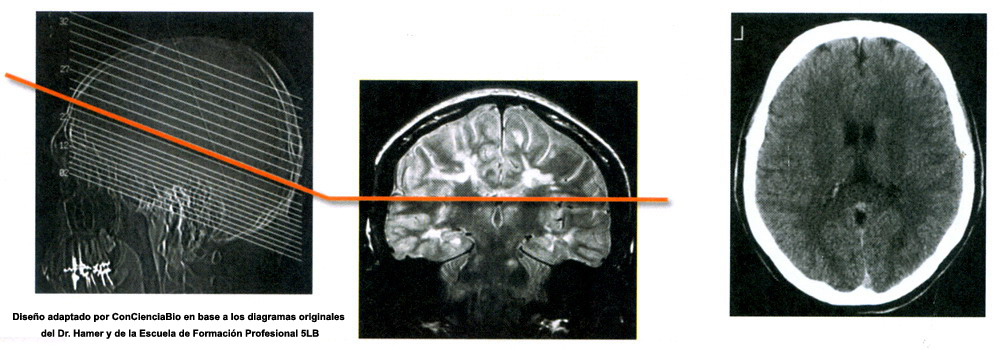

Costellazioni del midollo cerebrale

La costellazione del Midollo Cerebrale implica un conflitto attivo di svalutazione nei due emisferi cerebrali, ad esempio: le due ginocchia. La lateralità deve essere presa in considerazione.